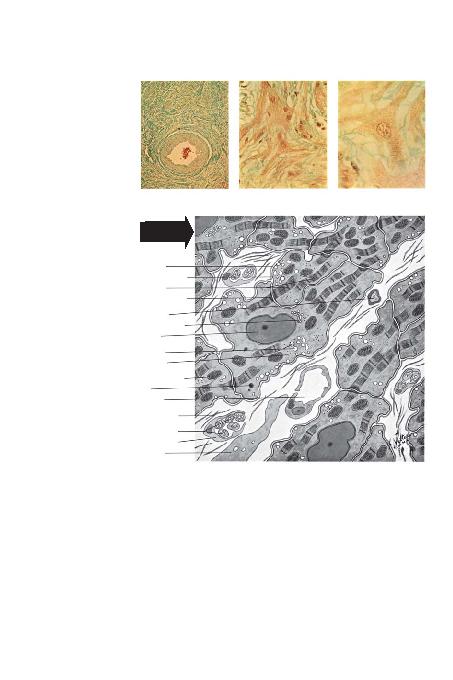

SANTRAL ARTERNODU, LDO/RU IfiINLAR HALTADIR (GOLDNER BOYASI, X10)

BAZAL

MEMBRAN

MYELS

SARKOPLAZMRET

KOLAJEN L

SCHWANN HÜCRELER<

TARAFINDAN ÇEVRE-

LENMS

SARKOZOM

(M

PLAZMA MEMBRANI

MYOF

GOLG< APARATI

R

L

KAP

F

NÜKLEUS

SHÜCRELER A/I (GOLDNER BOYASI, X160)

SDETAYLARI (GOLDNER BOYASI, X400)

SULTRAMYAPISI